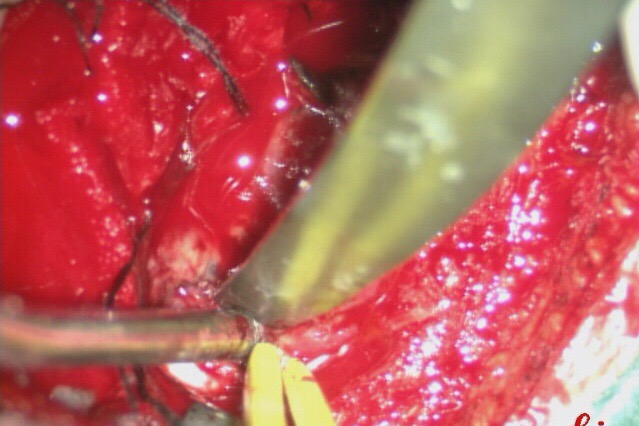

沿着肿瘤边缘分离肿瘤。

完整切除肿瘤。

手术用时3小时55分钟.完整切除肿瘤。